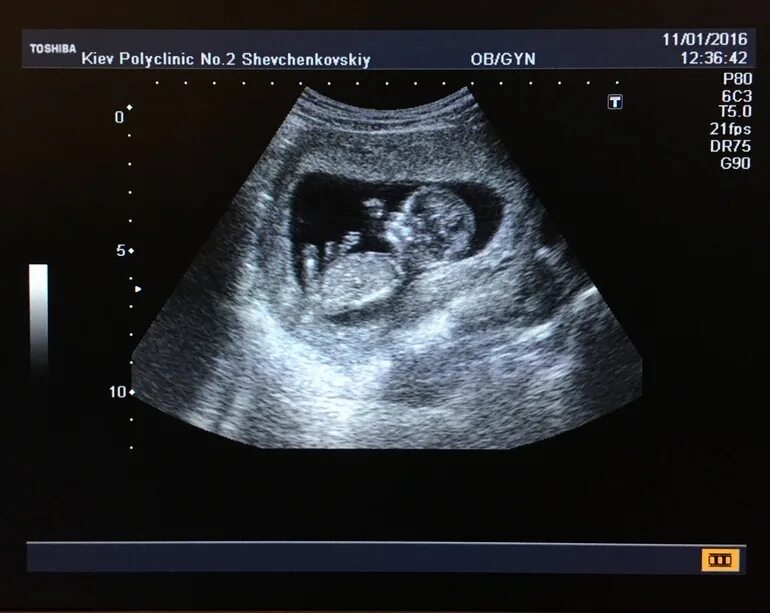

Малыш на первом скрининге